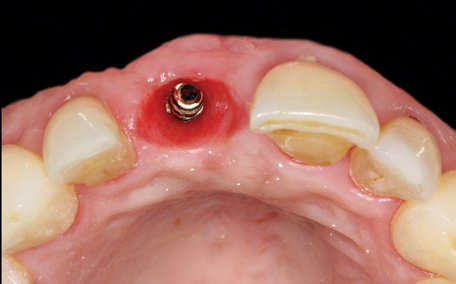

4. Facial and occlusal views of initial clinical presentation of tooth No. 8.

Figure 4

5. Facial and occlusal views of initial clinical presentation of tooth No. 8.

Figure 5

A 56-year-old female patient was referred for the evaluation of tooth No. 8 (Figure 4 and Figure 5). A periapical radiograph indicated that the tooth had undergone apicoectomy and received an excessively long post (Figure 6), and a cone-beam computed tomography (CBCT) scan of the site revealed a lack of buccal plate bone (Figure 7).